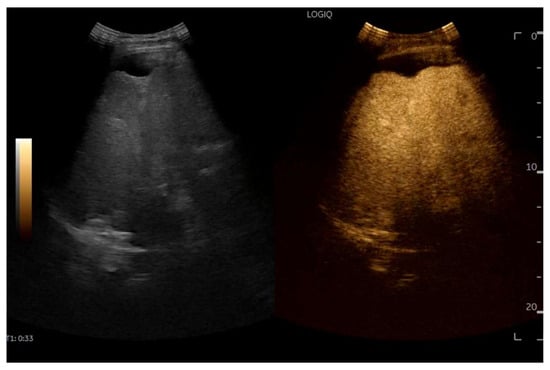

CEUS is valuable for characterizing the contrast enhancement patterns of liver nodules [68,69,70,71]. In Europe, the US contrast agent SonoVue® (sulfur hexafluoride; Bracco, Milan, Italy) is approved only for intravenous applications in patients over 18 years of age [72]. CEUS use in Fontan patients remains limited due to their frequent collateral circulation with right-to-left shunts, which is considered a contraindication in Europe but not in the United States. Beyond structural liver changes, CEUS reveals markedly heterogeneous hepatic enhancement with mosaic or reticular patterns, mainly due to slow and reduced enhancement near congested hepatic veins—one of the most common imaging features of FALD [54,73]. Anecdotal experience suggests that CEUS demonstrates heterogeneous and decreased liver enhancement in the portal venous phase, similar to cirrhosis of other etiologies (Figure 14, Figure 15). Abnormal enhancement is more prominent at the liver periphery than centrally, while the hypertrophic caudate lobe often shows more homogeneous enhancement. In patients with FALD, the altered hemodynamics resulting from chronic hepatic venous congestion and low cardiac output can significantly influence CEUS dynamics. Despite these circulatory changes, CEUS in FALD generally preserves the standard temporal enhancement pattern. The hepatic veins, although congested, do not typically show early enhancement, as microbubble distribution primarily reflects arterial input. The systemic hypokinetic circulation characteristic of FALD may lead to delayed arterial arrival times and a prolonged transit of contrast, especially in the background of the liver. Nonetheless, FNH-like nodules frequently exhibit intense and early arterial-phase hyperenhancement, suggesting preserved or increased arterial supply in these lesions. This contrast behavior is essential for lesion characterization.

Figure 14.

Contrast-enhanced ultrasound (CEUS) in the late phase shows the appearance of hypo-vascular areas due to varying degrees of congestion and hepatic alteration. These areas may mimic malignant nodular lesions with early washout.

Figure 15.

CEUS exam showing late heterogeneous enhancement in the arterial phase with evidence of hypo-enhanced areas, thus mimicking a malignant wash-out.